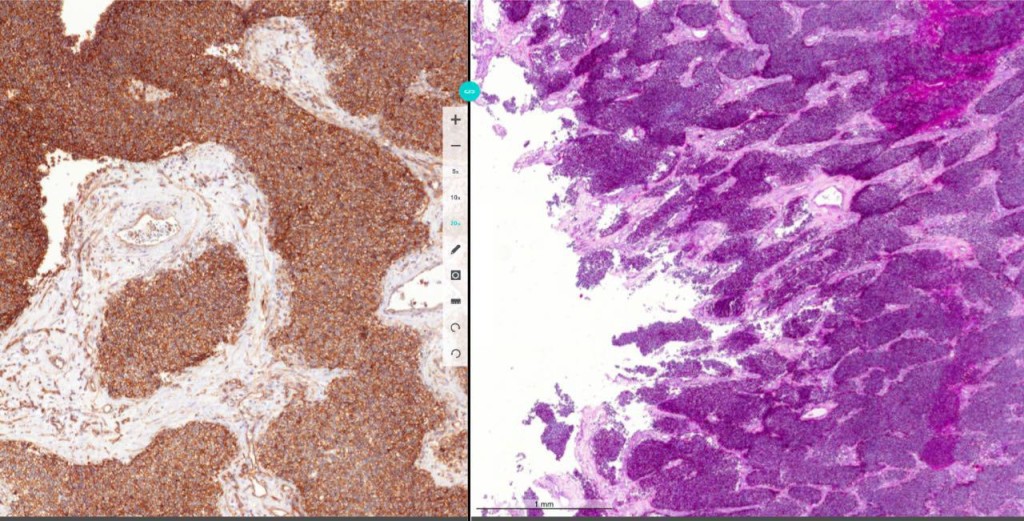

- В августе 2015 года мы решили провести диагностический конкурс для врачей-патологов. Партнеры из ЕС предоставили нам набор диагностических случаев, которые включают в себя клинические данные и стекла. Эта та совокупность информации, по которой в реальной практике патолог ставит человеку диагноз. В диагностике есть технологический этап: после проведения процедуры биопсии в лаборатории делают стекла, на которых находится тонкий срез ткани, обработанный специальными антителами. Второй этап – врач смотрит на это стекло под микроскопом и ставит диагноз. И на этом стекле, как вы понимаете, черным по белому ни кириллицей, ни латиницей не написано, что это за диагноз, а по классификации ВОЗ онкологических заболеваний несколько тысяч. То есть можно ошибиться не только в том, рак это или не рак, но и в том, какой именно это рак – а это не менее фатальная ошибка. В итоге нам предоставили примерно 14 кейсов, диагнозы по которым мы дополнительно подтвердили у наших партнеров из Великобритании и Норвегии, чтобы исключить ошибку. В конкурсе принимали участие примерно 250 патологов из России, а также врачи из Казахстана, Украины, Белоруссии и Израиля. По итогам этого конкурса мы решили запустить нашу образовательную программу на регулярной основе. Проект называется Pathology Puzzles.

- Наш проект нацелен на практикующих патологов – врачей, которые в первую очередь занимаются онкологической диагностикой. Обучение осуществляется онлайн в ходе регулярных диагностических раундов. Каждый месяц участники проекта получают доступ к новому диагностическому случаю (клинические данные и оцифрованные гистологические стекла), над которым могут работать совместно через облачную платформу Digital Pathology. Одно оцифрованное стекло может весить 2-4 Гб, а на один случай таких стекол может быть не одно, а тридцать одно. При этом облачная платформа позволяет работать с этой картинкой так быстро, как будто она находится у вас на компьютере. А самое главное, ее могут видеть сразу врачи из любой точки мира. Вот представьте, сотни специалистов, которые каждый день ставят десяткам человек диагноз, сидят вместе за одним микроскопом, смотрят в него, учатся. Например, такой кейс. Есть набор из 11 стекол и клинические данные: дерматология, пациенту 51 год, были жалобы на наличие выбухающего образования на коже медиальной поверхности нижней трети правой голени; других жалоб нет; было удалено и соответственно направлено на морфологические исследование. Здесь врачи обсуждают случай, высказывают свои точки зрения. Один из врачей считает, что это дерматофиброма (доброкачественная опухоль), а другой видит здесь рак. Врачи приводят свою аргументацию, и в конце концов приходят к неким точкам зрения. В итоге лидер раунда рассказывает, что это было на самом деле и как он это диагностировал. Конкретно в этом кейсе был диагностирован рак. И здесь же есть комментарии врачей, которые отмечают, что в своей практике, столкнувшись с подобным случаем, они бы диагностировали доброкачественную опухоль. Таким образом, врачи с помощью нашего проекта могут одновременно смотреть в один микроскоп, разбирать кейсы и перенимать опыт друг друга.